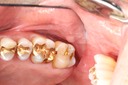

Scott Kanamori #29 caries removal